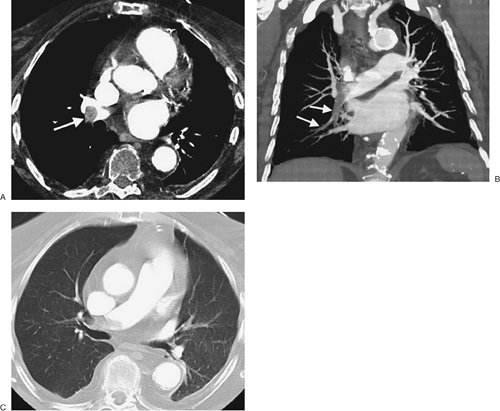

FIGURE 17-3. Acute PE. A: CTPA of a 77-year-old man with shortness of breath shows an intraluminal filling defect, surrounded by a rim of contrast, within the right lower lobe segmental pulmonary arteries (arrow). B: Coronal CTPA shows decreased caliber of arteries in the right lung compared with the left and filling defect within right lower lobe vessels. C: Catheter-based pulmonary angiogram confirms clot within right lower lobe vessels (arrows).